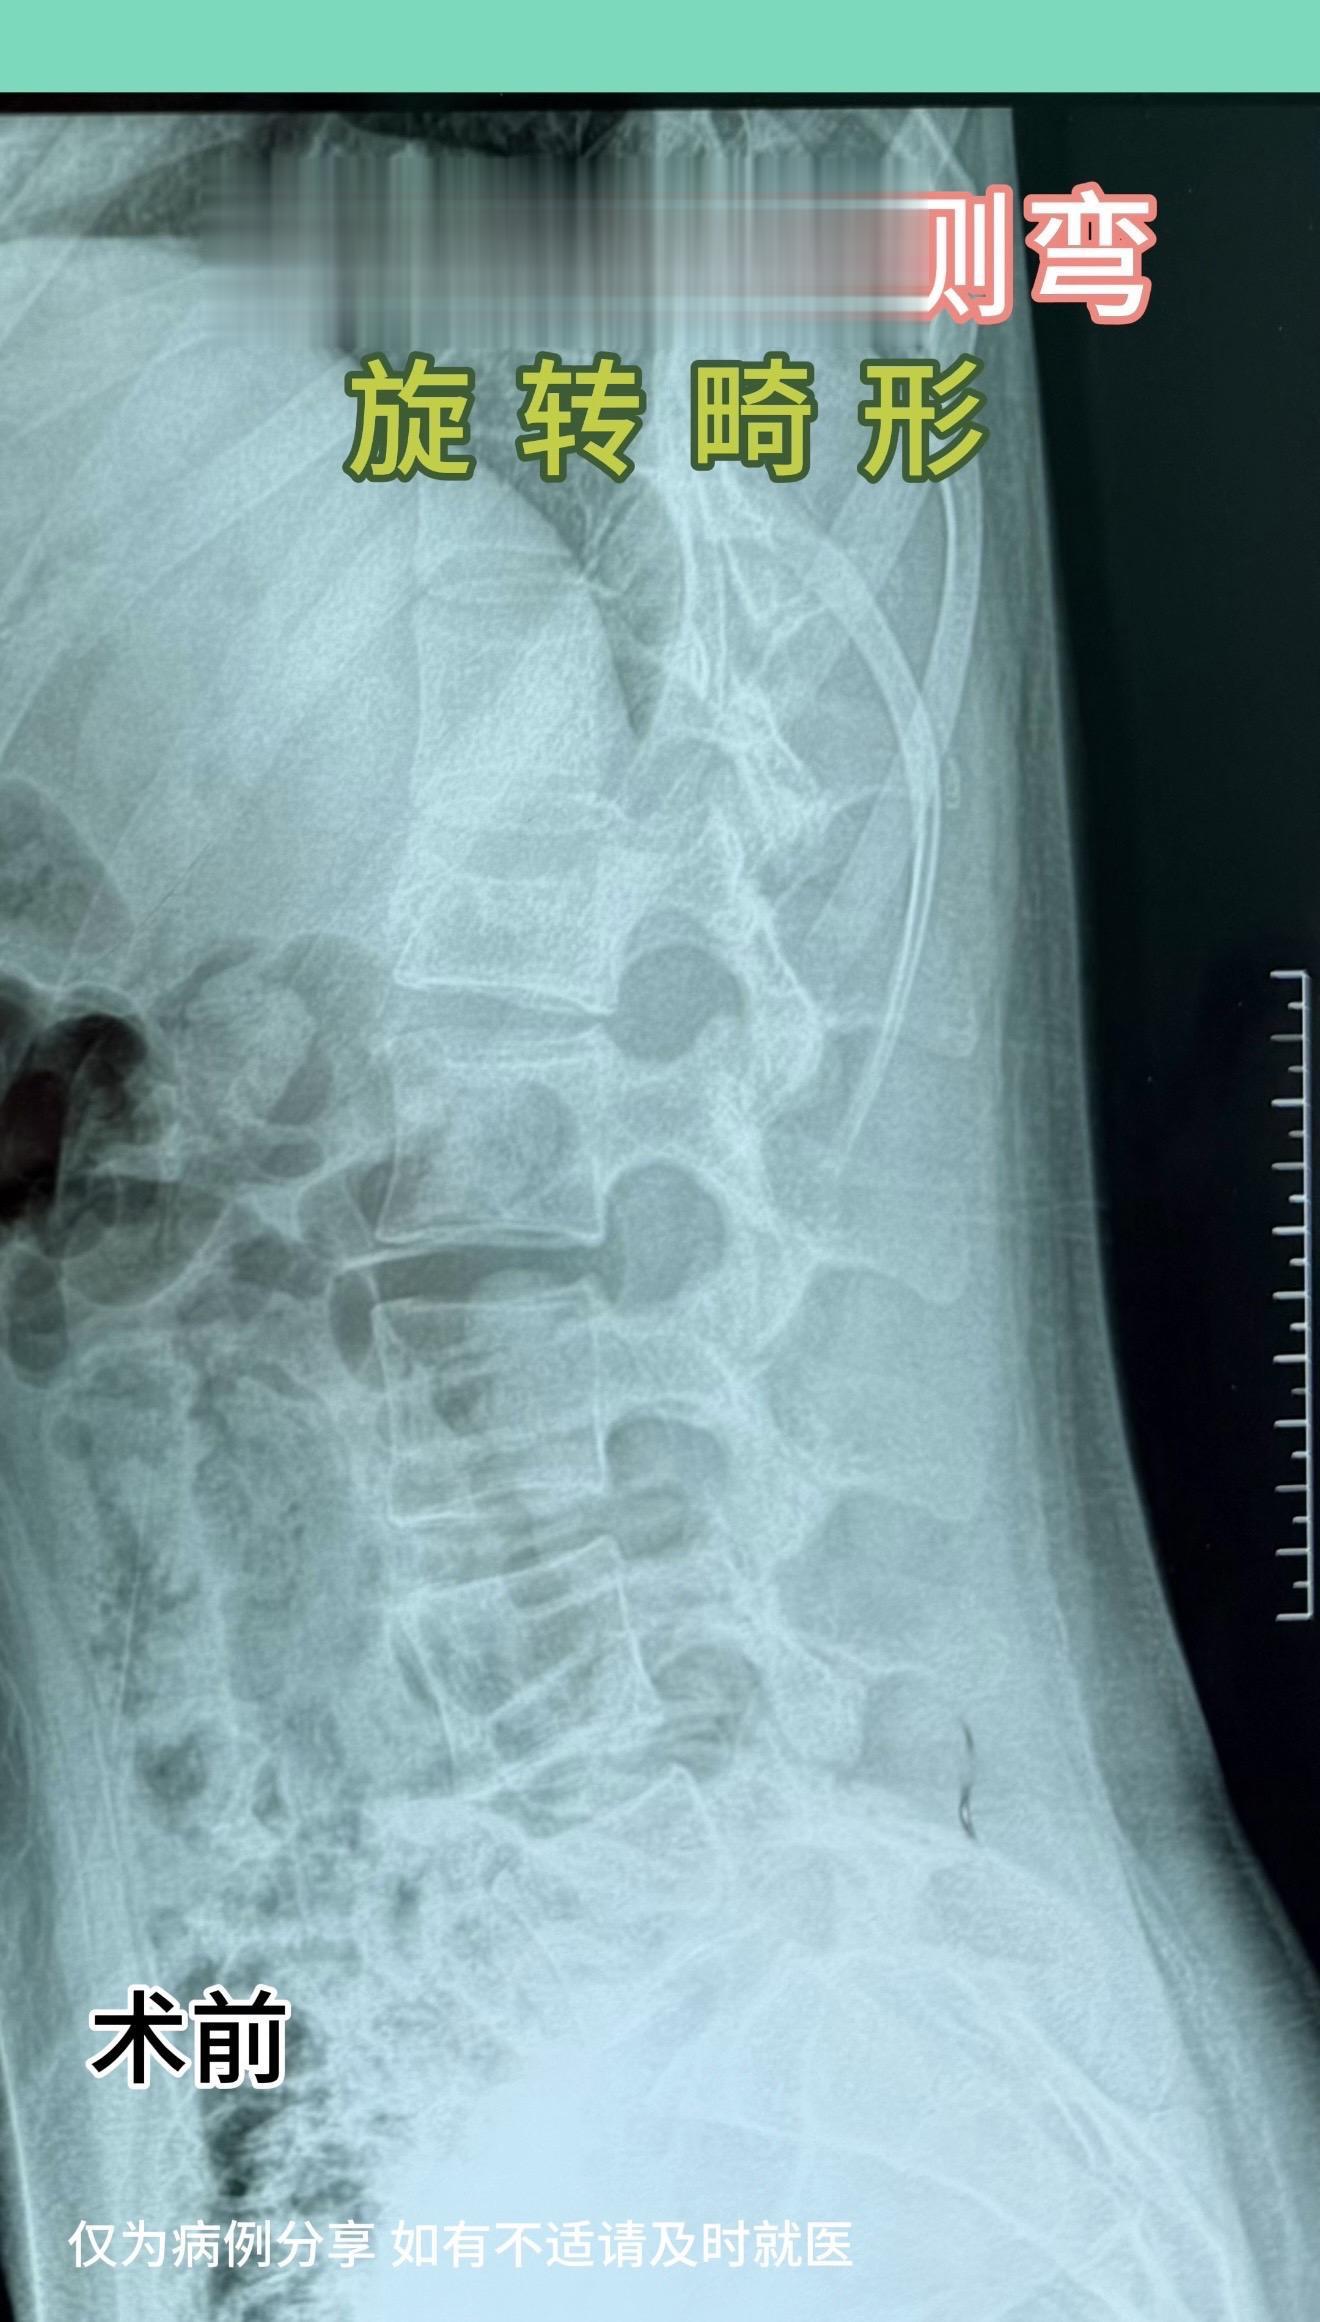

17岁女孩,车祸后腰1骨折伴侧弯,旋转畸形。术后畸形恢复好。